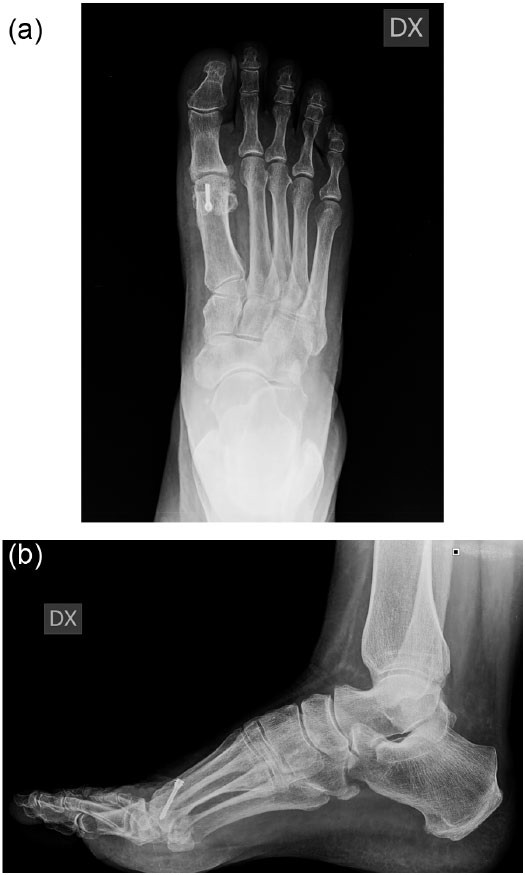

Risultato dopo osteotomia decompressiva